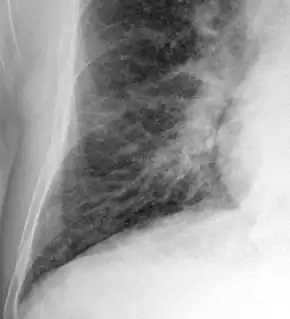

Chest X-ray

Chest X-rays are frequently used to aid in the diagnosis of CHF. In a person who is compensated, this may show cardiomegaly (visible enlargement of the heart), quantified as the cardiothoracic ratio (proportion of the heart size to the chest). In left ventricular failure, there may be evidence of vascular redistribution ("upper lobe blood diversion" or "cephalization"), Kerley lines, cuffing of the areas around the bronchi, and interstitial edema. Ultrasound of the lung may also be able to detect Kerley lines.[39]

-

Congestive heart failure with small bilateral effusions. -

Kerley b lines.